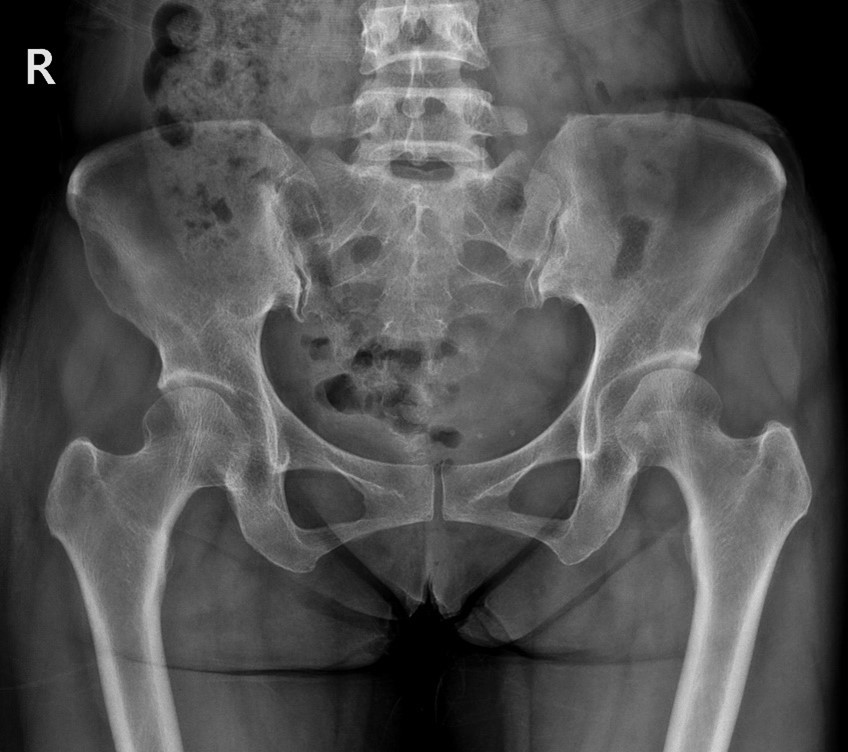

그림5.jpg 촬영 일시: 2025.05.30

<Fig 1. 이상근증후군으로 진단된 x-ray>

좌골신경이 지나가는 부위도

염증으로 인해 공간이 좁아져 있는 상태였고요.